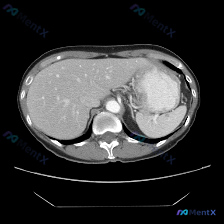

整理了一份很有意思的影像读片案例,一开始容易被提问带偏,仔细看下来其实是一个非常好的“临床思维”训练。 --- 病例基本情况 用户提出的问题是:“图像中描绘的具体异常是什么?脾脏病变”,附带了一幅腹部CT横断面(软组织窗)图像。 关键影像表现 我梳理了一下图像里的核心信息: 1. 脾脏:大小、形态正...

最近看到一个很有意思的影像分析场景,整理了一下思路和大家分享。 先看基础情况 用户预设了“脾脏病变”的方向,提供了一张腹部CT横断面软组织窗图像,从分析来看是增强扫描的动脉期或早期门脉期。 这张CT的核心表现 先整理一下明确的阳性/阴性信息: ✅ 图像质量:清晰度良好,无明显运动/金属伪影,软组织辨...

整理了一份很有意思的读片病例,差点被最初的提问带偏,分享一下思路: 病例背景 核心提问是“这张图里脾脏有什么病变?”,先来看影像的客观描述。 关键影像信息(增强CT横断面) 1. 扫描层面与质量:上腹部增强,对比度好,结构清。 2. 我们重点看的脾脏:边缘轮廓大致正常,未见明确局灶性低密度、高强化或...